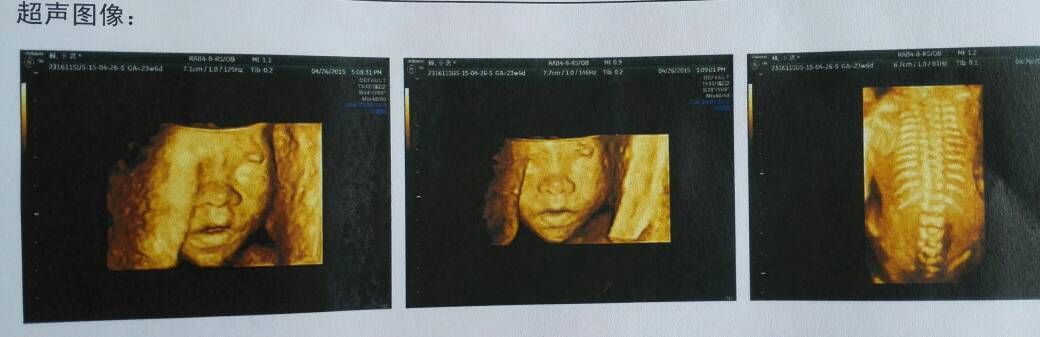

6个月的四维彩超单,请高手帮忙看看是男宝还是女宝~~男女宝都好。但实在郁闷,由于我们国家太多人重男轻女,医院都不敢说。而且已经做过3次超声检查了,想等到出生前最后再做一次检查,最近几个月不超声了。好奇啊,而且可以提前准备婴儿用品和心理准备,谁能看出来或者有经验的,给出合适的看法吧~~